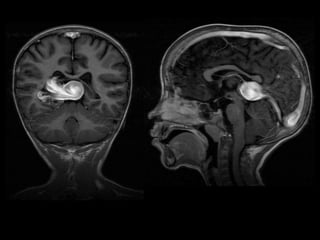

ESTUDIOS REALIZADOS:

TC CEREBRAL SIMPLE

08-06-2023.

TC SIMPLE DE CRANEO

08/06/2023

CORTE

AXIAL

CORONAL

SAGITAL

VOLUMEN: 25,1 CC

Lesión ocupante de espacio extraaxial

supratentorial a nivel de cisterna cuadrigeminal.

CONCLUSIONES: